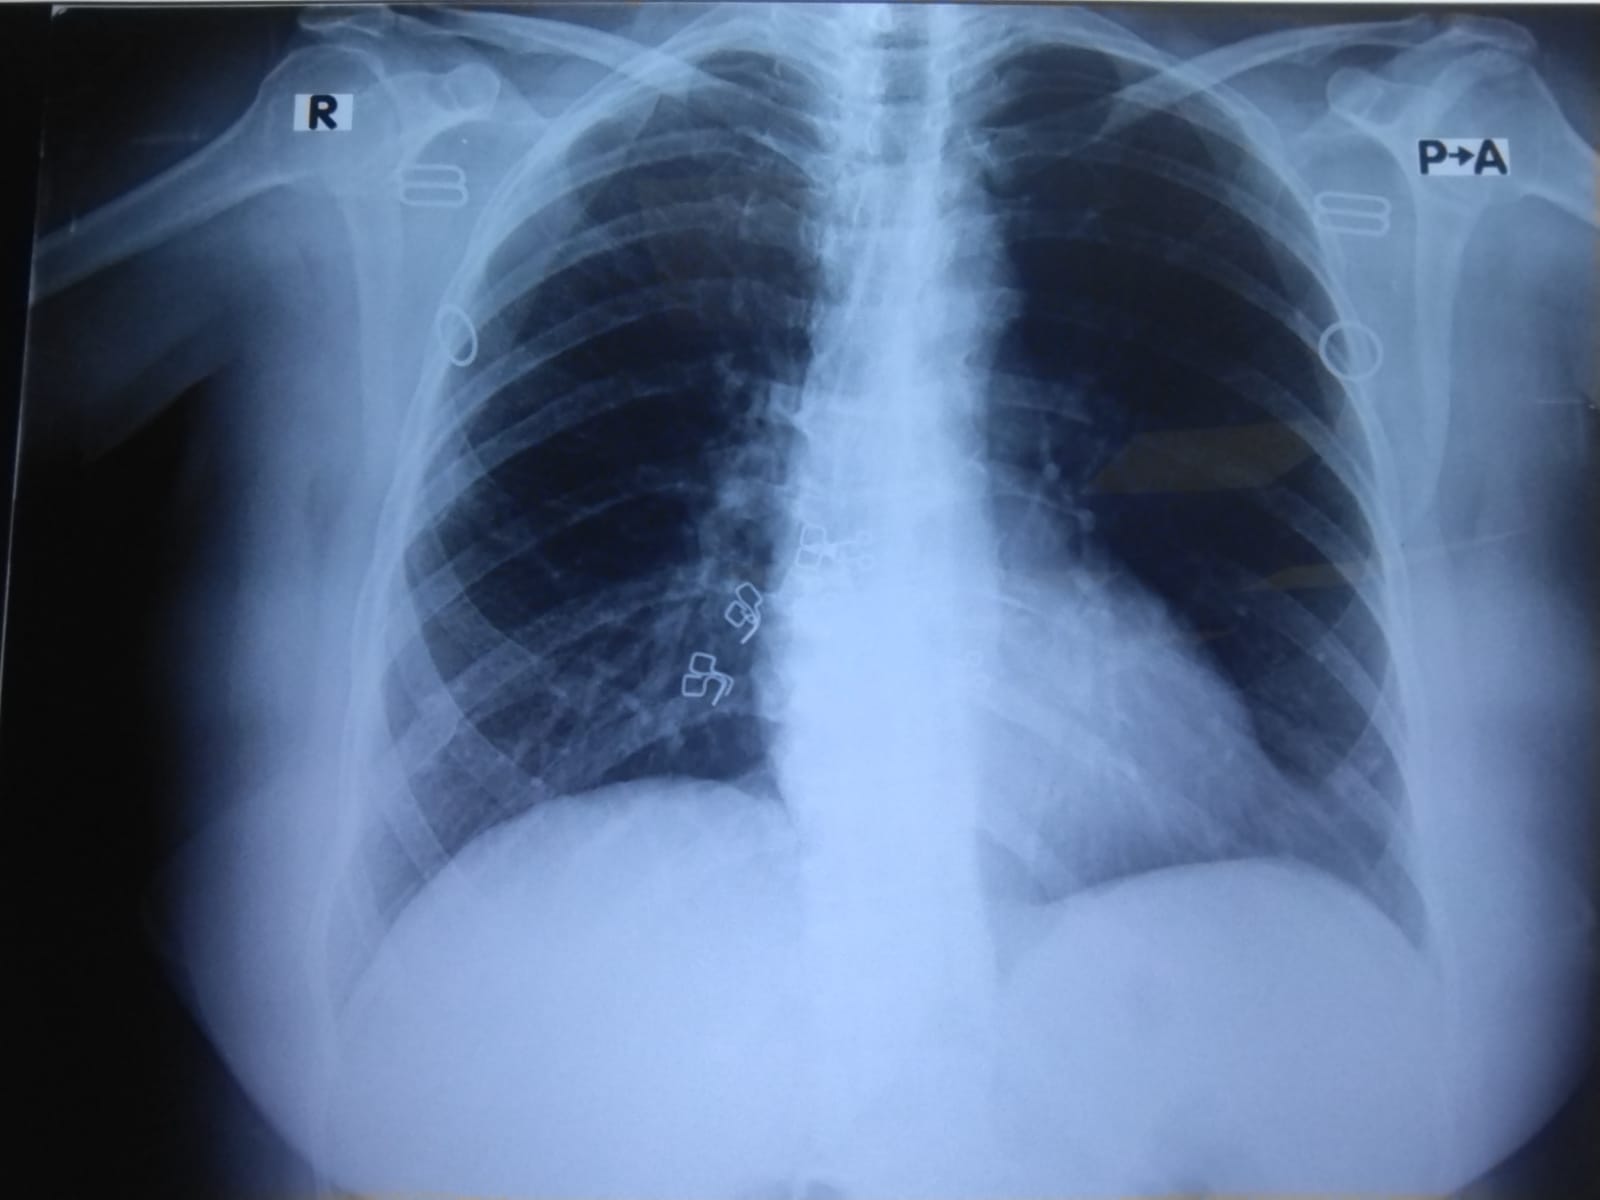

Is this Xray report fine?

x-ray is fine except for a possible old healed fracture right rib

but if covid test is positive, and patient is symptomatic keep an eye on patients oxygen saturation and manage according to clinical symptoms

? Lung fields are clear and quite good

Bones appear normal

Both Cp angles are acute

Cardiac silhouette appear normal

This is a good normal study

However if u suspect covid u should go for PCR or HRCT as X ray is not a modality to entirely rule In or rule out COVID pneumonia .

for a female 65 years old - this x- Ray is normal.

how ever patient history is important ,if covid is suspected then HRTC is best modality .